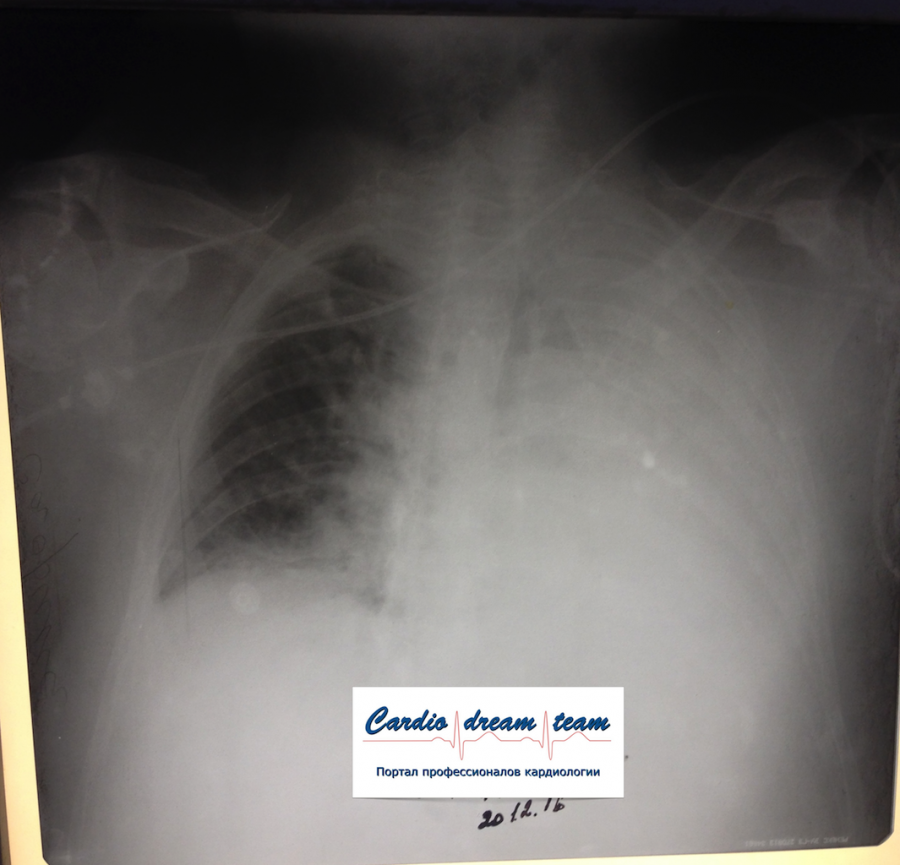

Ателектаз слева. Гнойный эндобронхит с закупоркой бронхов гноем.

Обсуждалось в Госпитале Ослабленных Сердец